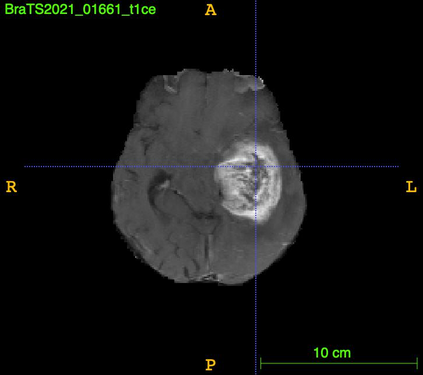

As information sources are usually imperfect, it is necessary to take into account their reliability in multi-source information fusion tasks. In this paper, we propose a new deep framework allowing us to merge multi-MR image segmentation results using the formalism of Dempster-Shafer theory while taking into account the reliability of different modalities relative to different classes. The framework is composed of an encoder-decoder feature extraction module, an evidential segmentation module that computes a belief function at each voxel for each modality, and a multi-modality evidence fusion module, which assigns a vector of discount rates to each modality evidence and combines the discounted evidence using Dempster's rule. The whole framework is trained by minimizing a new loss function based on a discounted Dice index to increase segmentation accuracy and reliability. The method was evaluated on the BraTs 2021 database of 1251 patients with brain tumors. Quantitative and qualitative results show that our method outperforms the state of the art, and implements an effective new idea for merging multi-information within deep neural networks.